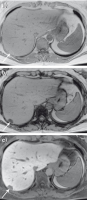

Abbildung 10a-c: Diagnose von Steatose, Fibrose und Zirrhose. (a) In dem T1-gewichteten MRT-Bild In-Phase zeigt sich ein inhomogenes Signal der Leber, hinweisend auf eine diffuse Parenchymerkrankung. (b) In dem T1-gewichteten MRT-Bild Opposed-Phase zeigt sich ein deutlicher inhomogener Signalabfall der Leber im Vergleich zum In-Phase-Bild als Ausdruck der deutlichen inhomogenen Steatose. (c) Nach Gabe von Gadoxetat zeigt sich eine deutliche inhomogene Kontrastierung der Leber mit fehlendener hepatobiliärer KM-Aufnahme im Bereich der fibrotischen Septen und eine verstärkte hepatobiliäre KM-Aufnahme im Bereich der Regeneratknoten, im Rahmen der begleitenden starken Leberfibrose/Zirrhose.